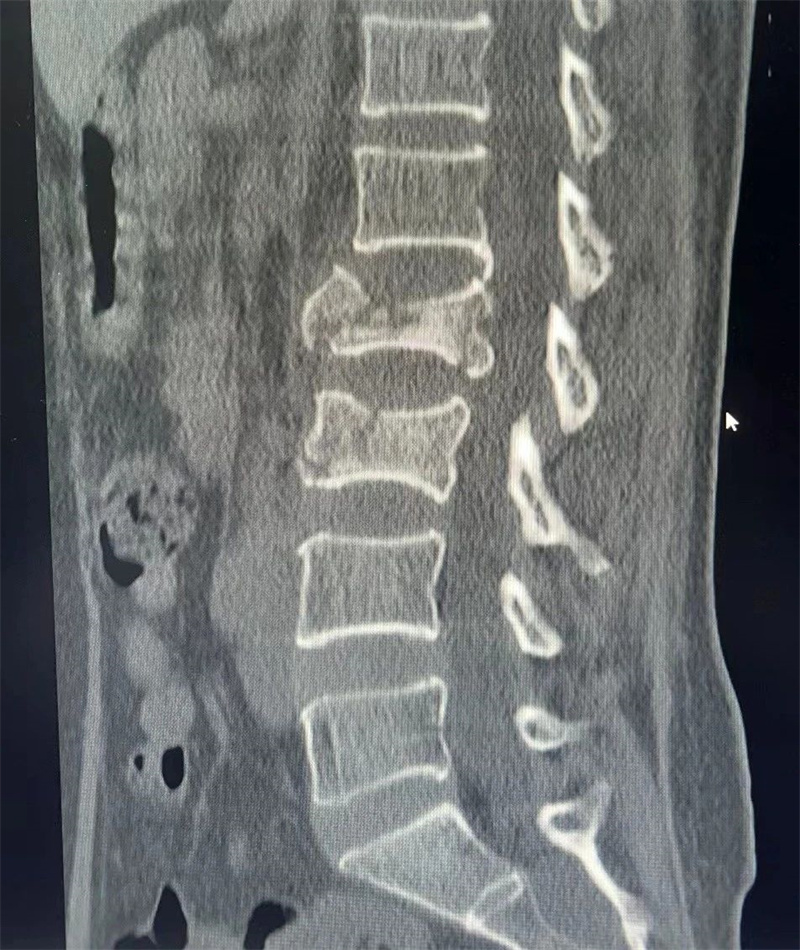

(術(shù)前患者影像學(xué)資料)

很快病情平穩(wěn),受傷5天后即由ICU轉(zhuǎn)入骨傷一科普通病房行腰椎骨折專(zhuān)科診治。骨傷一科戴賀主任立即組織團(tuán)隊(duì)為患者行專(zhuān)科診治。經(jīng)完善術(shù)前檢查后,患者腰2、腰3椎體均為爆裂骨折,中柱塌陷,嚴(yán)重影響了脊柱穩(wěn)定性,為了以后的生活質(zhì)量,需要進(jìn)行手術(shù)治療,且手術(shù)盡量應(yīng)在15天內(nèi)完成,神經(jīng)外科團(tuán)隊(duì)的積極治療為患者的快速康復(fù)打下了基礎(chǔ)。又因患者存在腦出血,且需行全麻,患者及家屬都非常擔(dān)心手術(shù)中患者是否有腦出血風(fēng)險(xiǎn)。在術(shù)前,麻醉科汪世高主任對(duì)患者行術(shù)前評(píng)估后,組織專(zhuān)家團(tuán)隊(duì)擬定了周密的圍手術(shù)期管理計(jì)劃。術(shù)中麻醉醫(yī)生劉鵬對(duì)患者進(jìn)行了精準(zhǔn)調(diào)控和嚴(yán)密監(jiān)護(hù),將患者風(fēng)險(xiǎn)降至最低,確保手術(shù)安全順利進(jìn)行。